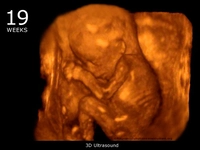

• 19. Hafta: Fetüs, yavaş yavaş daha fazla hareket etmeye başlar. Anne adayı, karnındaki büyümeyi daha belirgin hissedebilir.